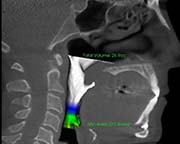

3 weeks post surgery

Surgical Plan